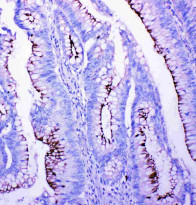

ARG40835 anti-Profilin 2 antibody IHC-P image

Immunohistochemistry: Paraffin-embedded Human intestinal cancer tissue. Antigen Retrieval: Heat mediation was performed in Citrate buffer (pH 6.0, epitope retrieval solution) for 20 min. The tissue section was blocked with 10% goat serum. The tissue section was then stained with ARG40835 anti-Profilin 2 antibody at 1 µg/ml, overnight at 4°C.